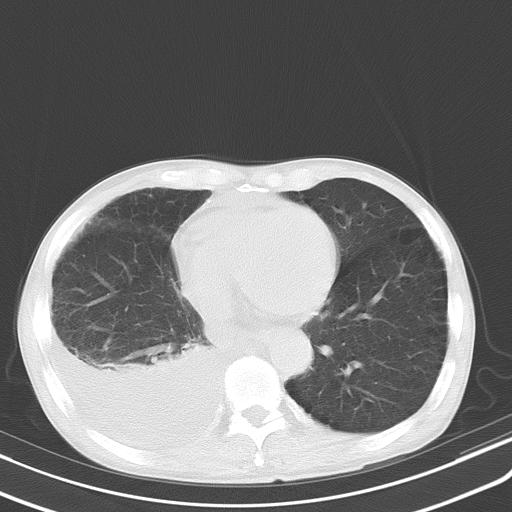

男性 75  咳嗽 一周前发热最高达39

右肺继发型tb并右侧tb性胸腔炎,右侧胸腔大量积液并右下肺膨胀不全,慢支肺气肿、多发肺大泡。建议抽胸水实验室检查并复查排除恶性在占位。

右上肺继发型肺结核,右胸腔中等量积液。

左上肺大泡。

结核的基础上有纵隔淋巴结肿大,右侧有胸水,但右侧纵隔反而窄,说明有肺有不张。

再就是右下肺有块影,和不张混合,还是不能除外肺癌。

补充材料,患者2月份ct片大致正常,双侧胸腔积液,2月份抽胸水未发现ca细胞,现患者发热,痰多,各气管通畅,

1)右肺继发型肺结核。2)左肺胸膜下多发性肺大泡。3)右侧胸腔积液。